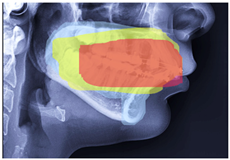

2.2. ROI Handcrafted Feature Detection

2.3. ROI Identification, YOLO-UNet-Based